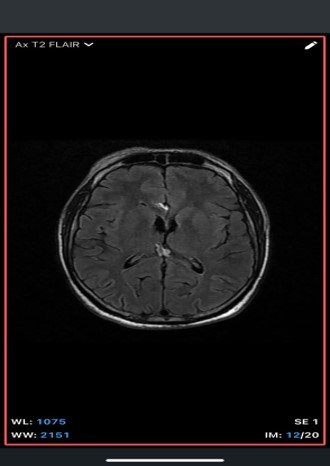

An extra-axial TI/T/Flair hyperintense lesion in midline at the inferior edge of the interhemispherie fissure extending along the superior margins of the corpus callosum with areas of blooming consistent with calcification and no post contrast enhancement –likely pericallosal lipoma.

• MRI

• T1-weighted: Hyperintense (fat signal).

• T2-weighted: Variable, usually hyperintense; may show chemical shift artifacts.

• Fat-suppressed sequences: Complete signal suppression confirms fat composition.

• Post-contrast: No enhancement.